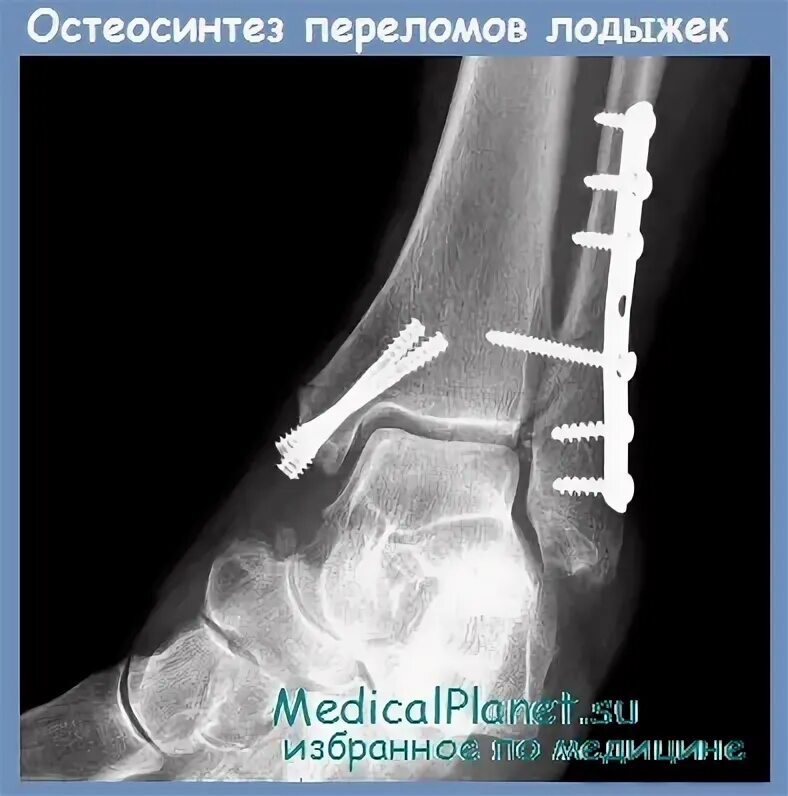

После остеосинтеза лодыжек